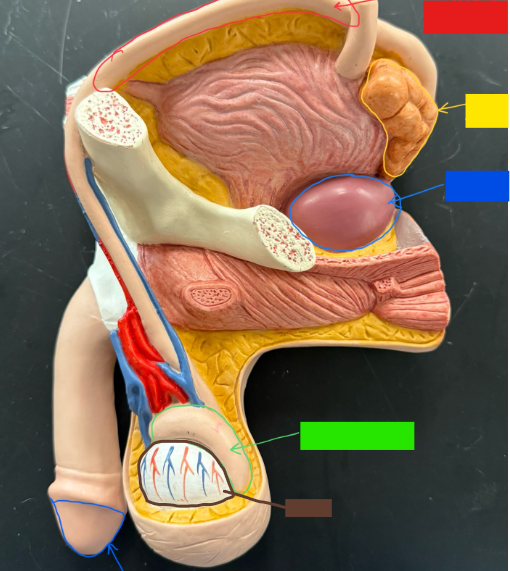

What is the name of the red box?

Vas deferens

What is the name of the yellow box?

Seminal vesicle

What is the name of the blue box?

Prostate

What is the name of the light green box?

Epididymis

What is the name of the light blue box?

Prepuce

What is the name of the blue box?

Corpus spongiosum

What is the name of the light green box?

Glans penis

What is the name of the red box?

Seminiferous tubules

What is the name of the black box? X2

Prostate

What is the name of the brown box?

Testis